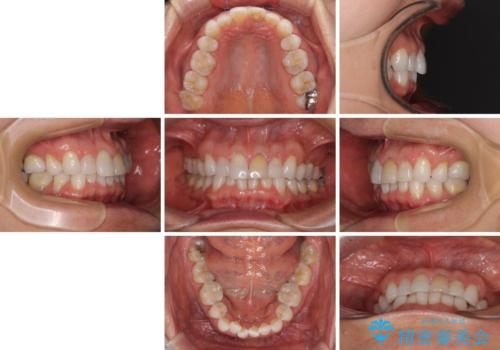

矯正治療の後戻り インビザライン・ライトでの再矯正

- 上下前歯を中心に、以前行った矯正治療の後戻りが気になるとのことで来院された患者様です。

後戻りは軽度であったため、インビザライン・ライトにて治療を行うこととしました。

矯正治療後は、再度後戻りすることを極力回避するために、下顎前歯の舌側を細いワイヤーを用いて保定することとしました。